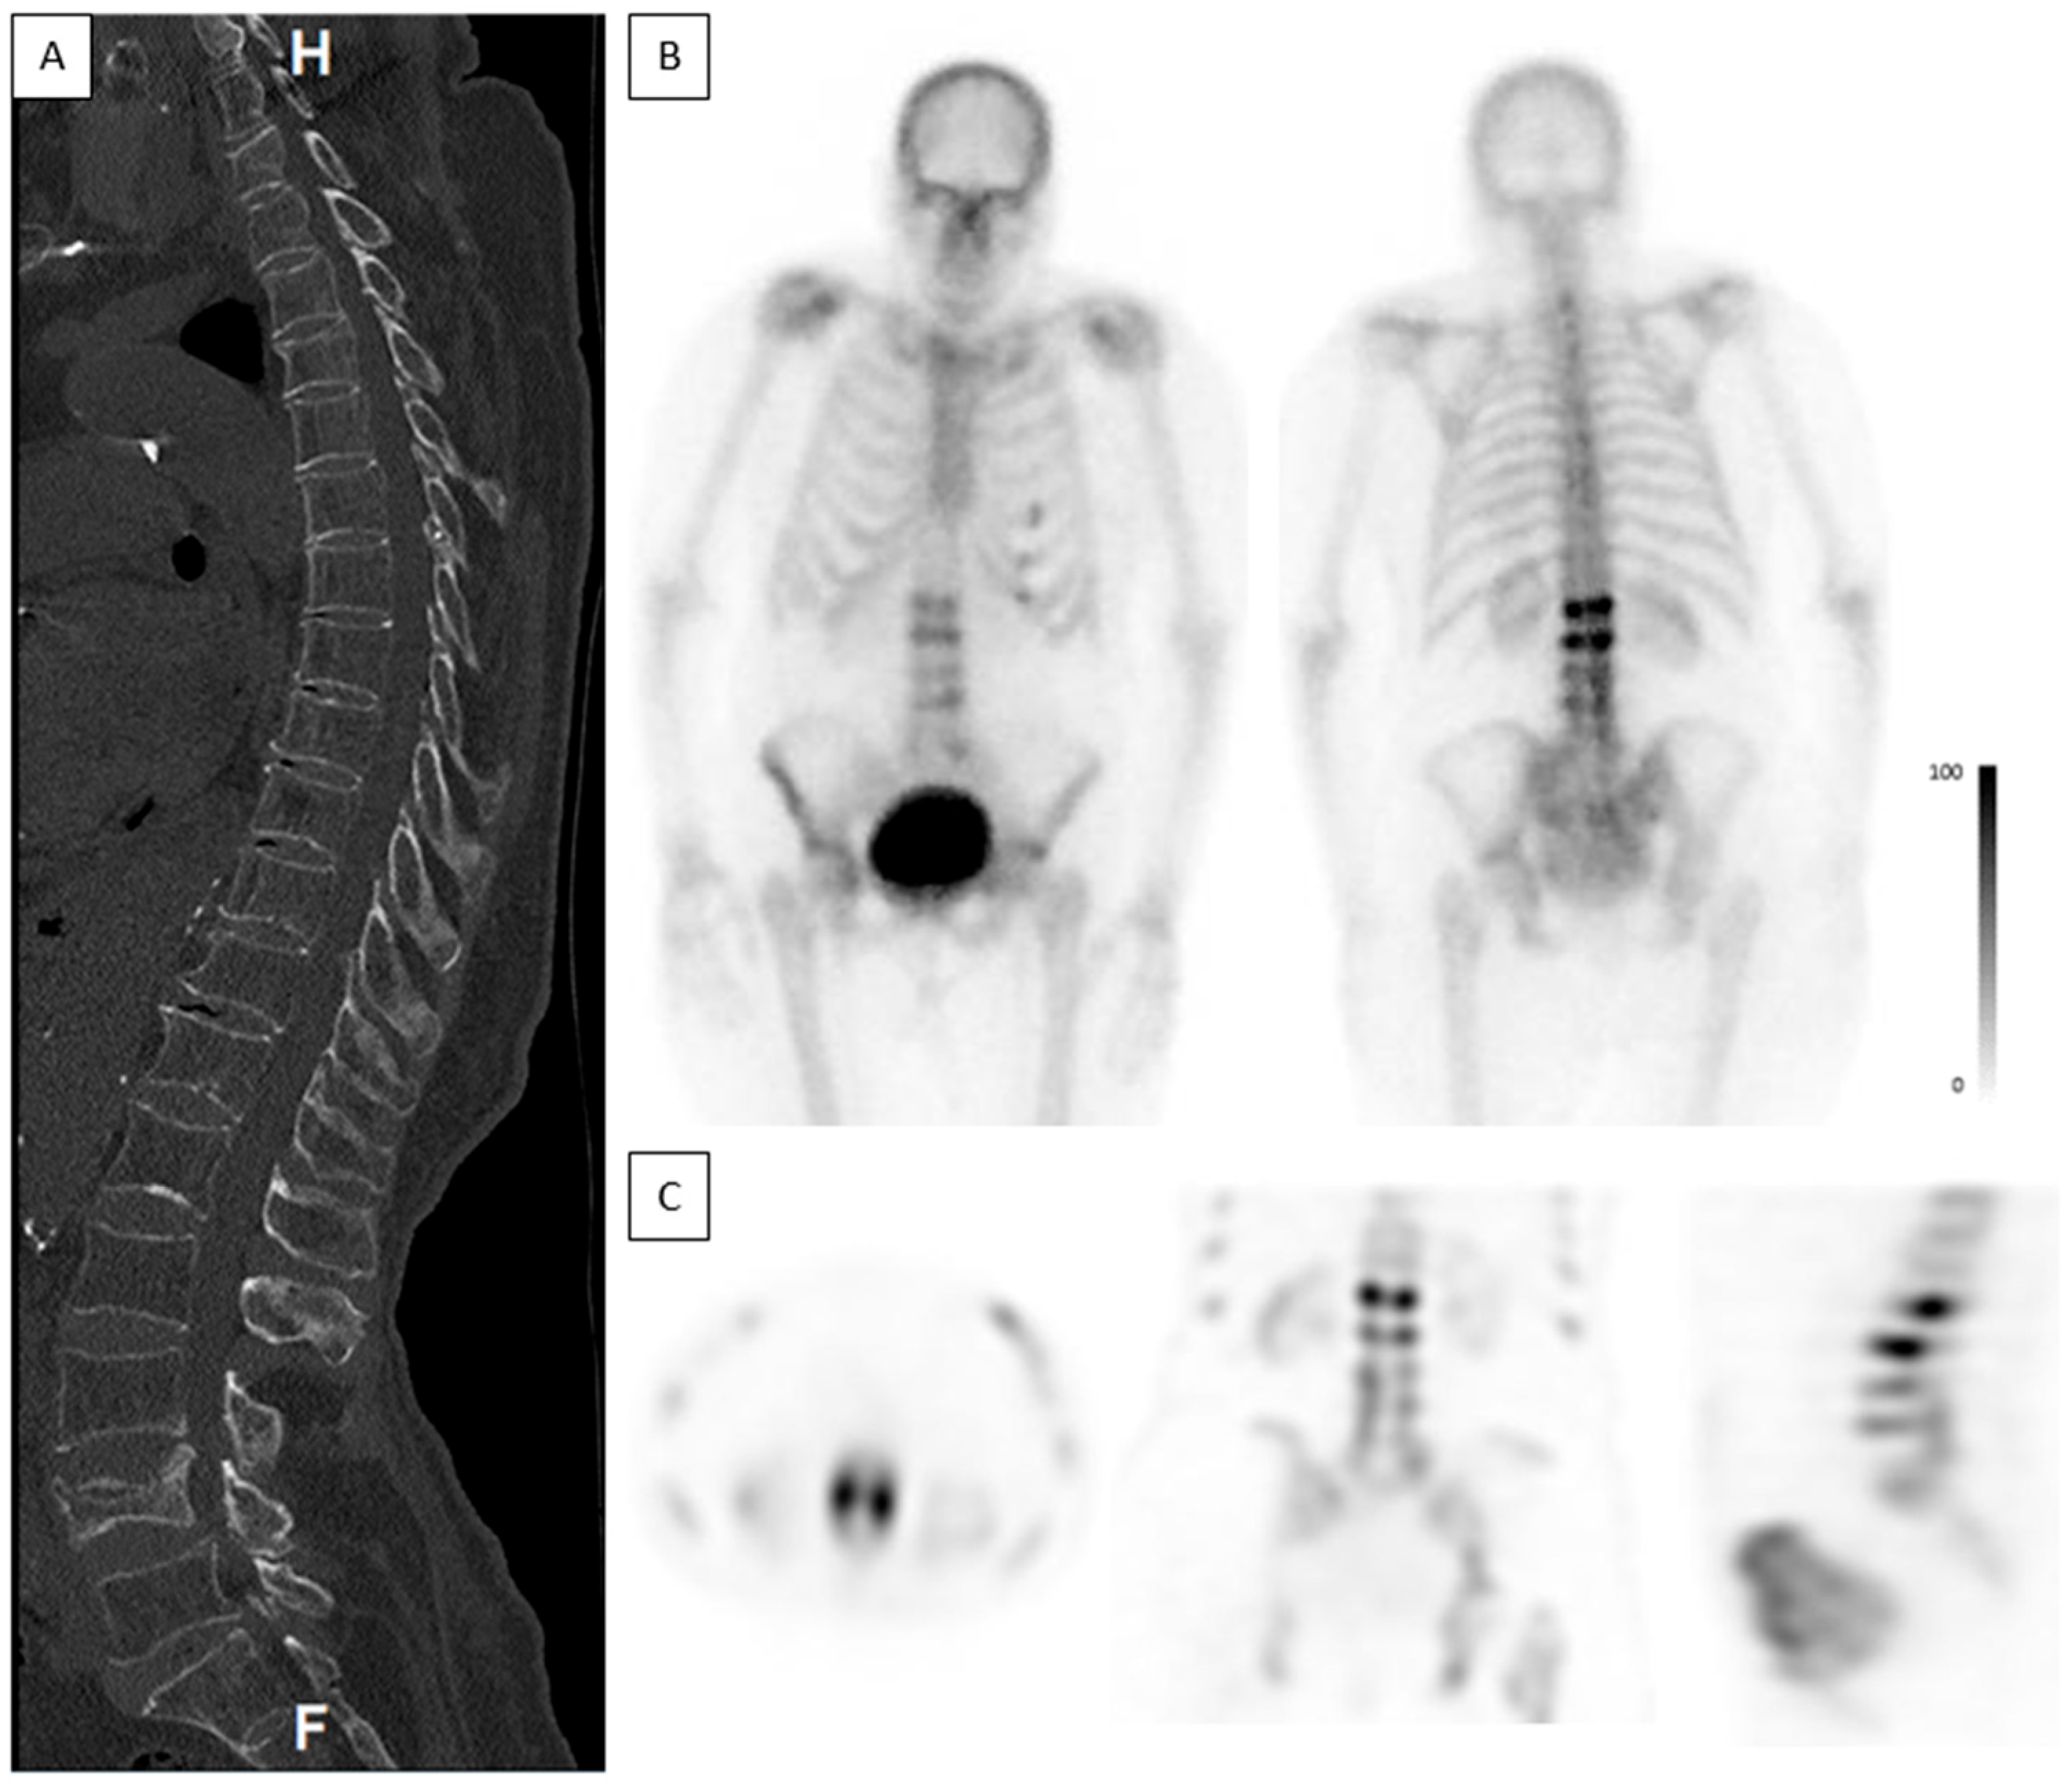

Figure 7. Low-intensity uptake in an acute ankylotic VCF. A 72-year-old male. CT was acquired on the day of injury and bone scintigraphy was performed 3 days after the injury. (A)—Coronal, axial, and sagittal spine CT show an acute ankylotic fracture in L2 and a fracture involving an osteophyte in L1 (white arrow). (B)—Planar anterior and posterior bone scintigraphy do not show any increased uptake in L2. (C)—Coronal, sagittal, axial, and MIP SPECT show only low-intensity uptake in L2 (black arrow).

SPECT studies are known to increase the sensitivity and specificity of BS [32]. In the current study, SPECT images were very helpful in detecting low-intensity uptakes that would have been missed using only planar images, as shown in Figure 7. They were also paramount for determining the exact location of the fractures and were easier to compare to the recently performed spine CT. The combined viewing of the SPECT and CT images was helpful in differentiating uptakes caused by degenerative changes vs. true fractures. If spine CT is not acquired prior to the bone scintigraphy in patients with suspected acute VCF, SPECT/CT should be performed when available.